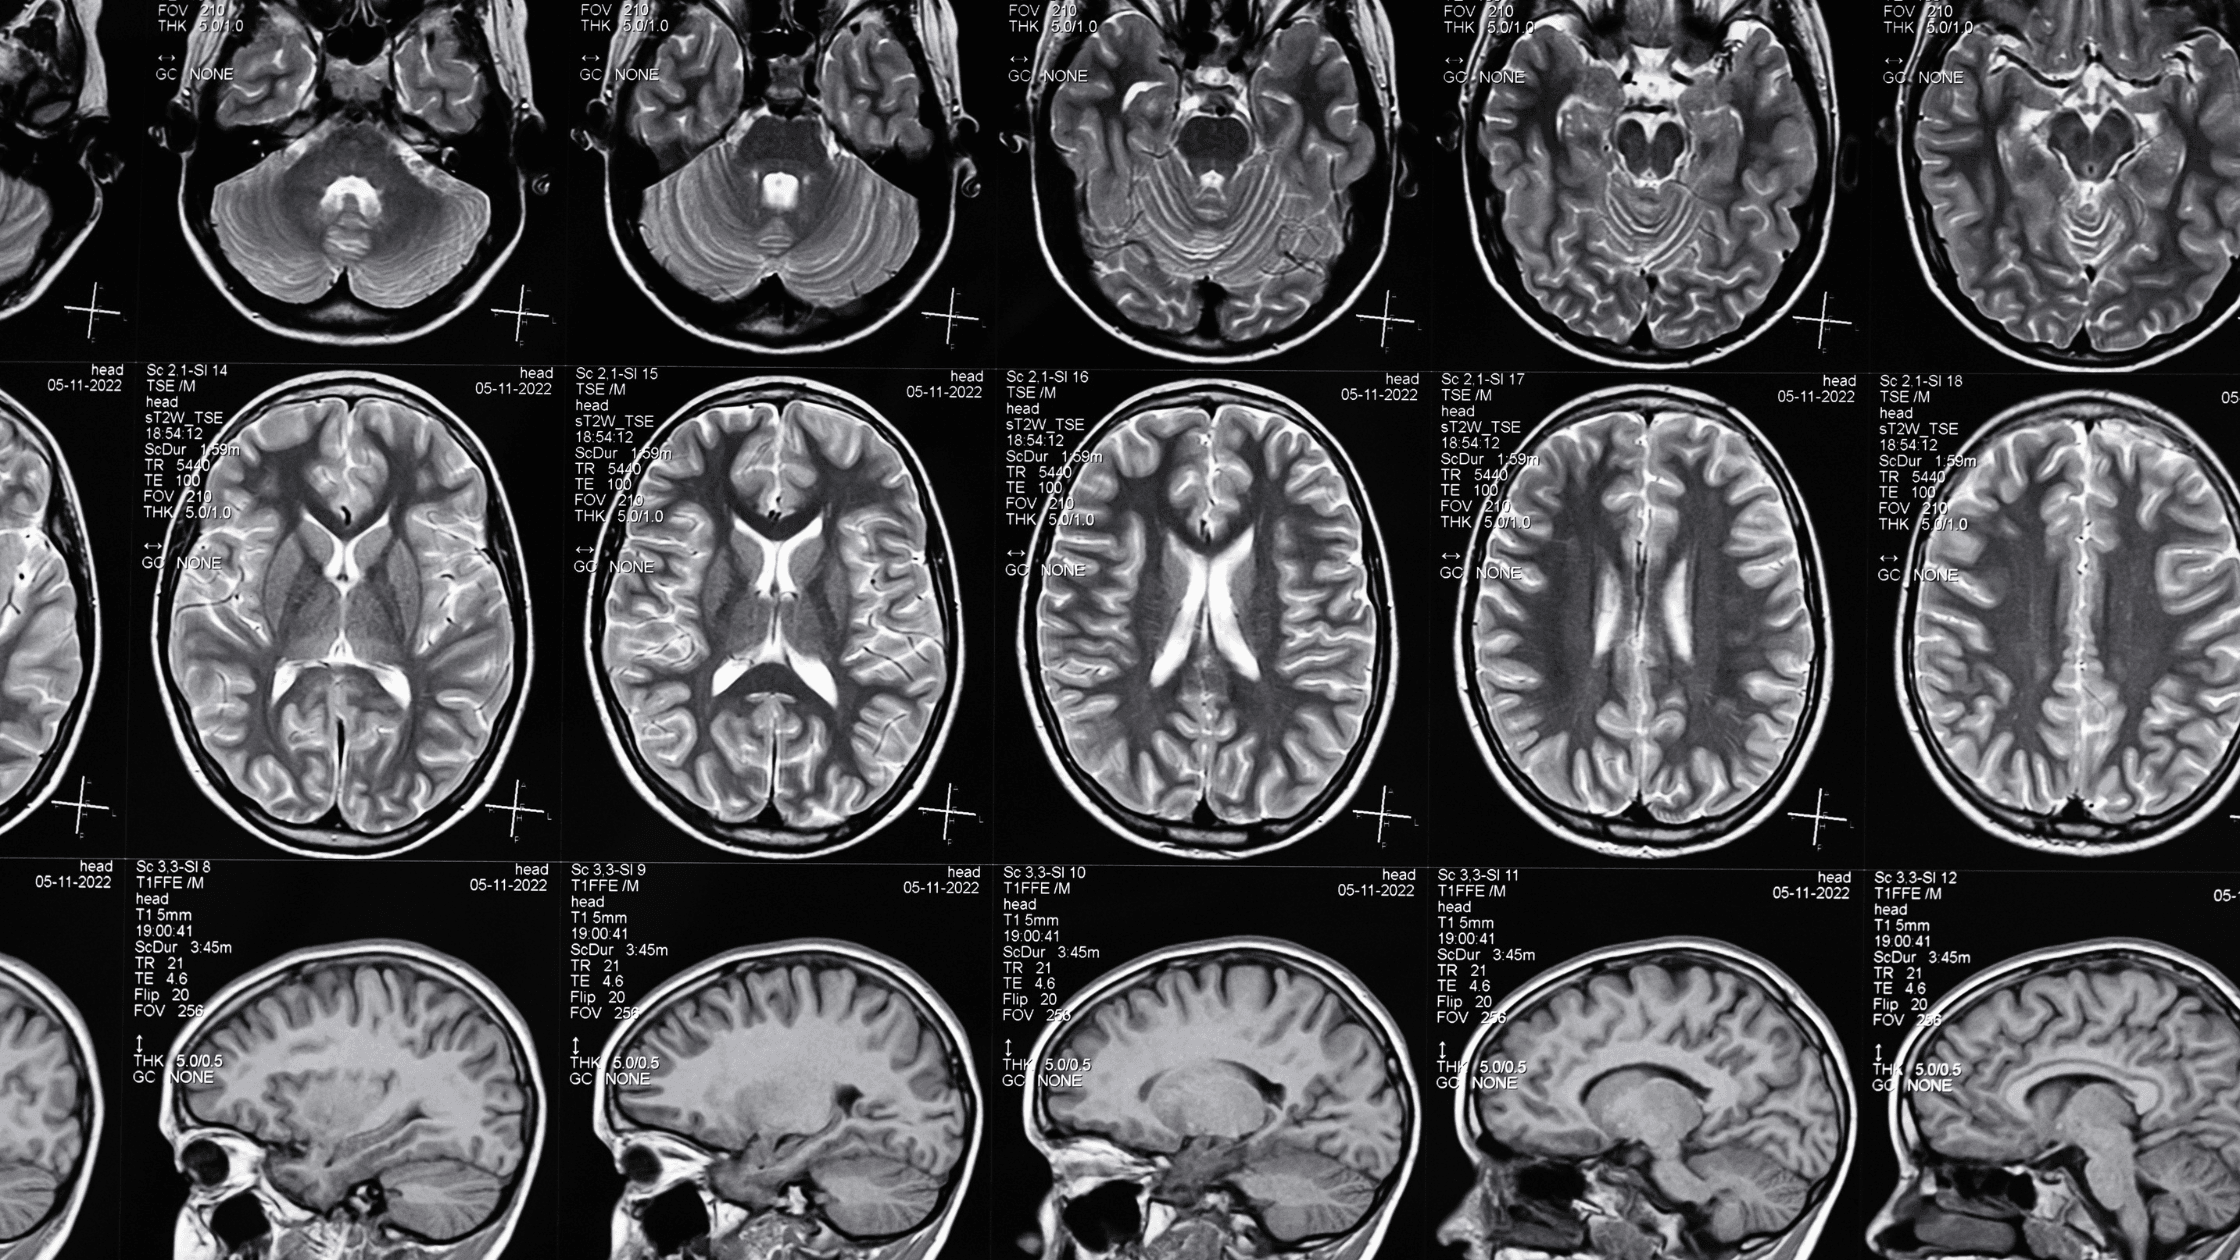

• Resonancia Magnética (RM): es la prueba de imagen de referencia; proporciona imágenes detalladas del cerebro, permitiendo identificar anomalías estructurales que pueden estar asociadas con las crisis epilépticas. Existen varios tipos de lesiones que pueden verse en la RM en pacientes epilépticos, como las malformaciones corticales, esclerosis hipocampal, tumores, etc. Cada vez podemos identificar más lesiones, aunque sean sutiles, debido a los equipos de RM de última generación.